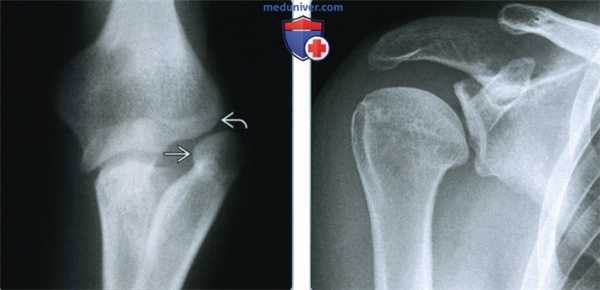

• Отсутствие/гипоплазия головки лучевой кости:

о Асимметрично

о Головка лучевой кости может подвывихнуться или сместиться

о Гипоплазия головки плечевой кости и латерального мыщелка

о Выступающий медиальный мыщелок

о Создается положительная локтевая деформация в области запястья

о Вальгусная деформация локтевого сустава

о Ограничение подвижности

• Гипоплазия плеча, таза

(Слева) Рентгенография в ПЗ проекции: определяется характерное врожденное смещение головки лучевой кости. Латеральная поверхность сустава патологическая, с морфологической деформацией как головки лучевой, так и головки плечевой кости.

(Справа) Рентгенография в ПЗ проекции: определяется гипоплазия суставной поверхности лопатки и головки плечевой кости. В то время как колено и локоть почти полностью вовлечены в синдром ногтя-надколенника, гипопластические изменения могут обнаруживаться в любом суставе.